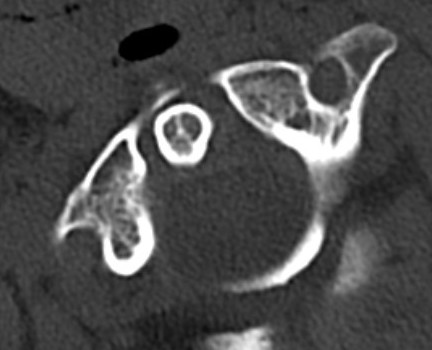

CT Scan

Atlanto-axial rotatory instability

Classification Fielding & Hawkins

| Type I |

Unilateral facet subluxation / dislocation ADI < 3 mm |

Transverse ligament intact | Most common |

| Type II |

Unilateral facet subluxation / dislocation Anterior displacement of the atlas by 3–5 mm ADI 3 - 5 mm |

Transverse ligament injury | |

| Type III |

Bilateral facet subluxation / dislocation Anterior displacement of atlas by more than 5 mm ADI > 5 mm |

Alar and tranverse ligament deficient Both lateral masses displaced anteriorly |

|

| Type IV | Posterior displacement of atlas | Ondontoid process deficient or fractured |

Rare Highest risk of neurological injury |